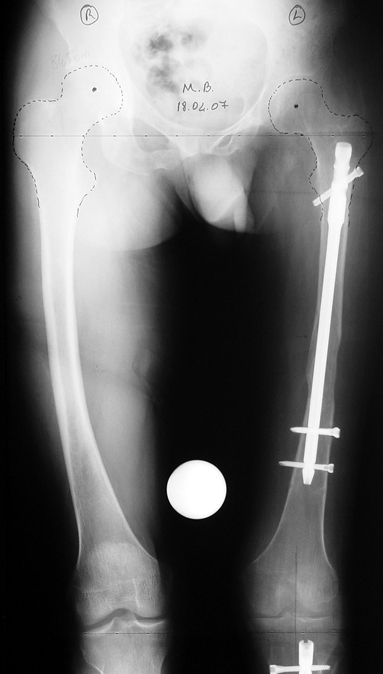

3. POSTTRAUMATIC LOWER LIMB SHORTNESS (MALUNION)

This type of shortness occurs after a fracture heals in a shortened position. Most cases are seen in adults and can be treated with one lengthening operation. Additional deformities can be corrected simultaneously. Most of these cases can be treated with lengthening over nail or just corrections and intramedullary nailing.